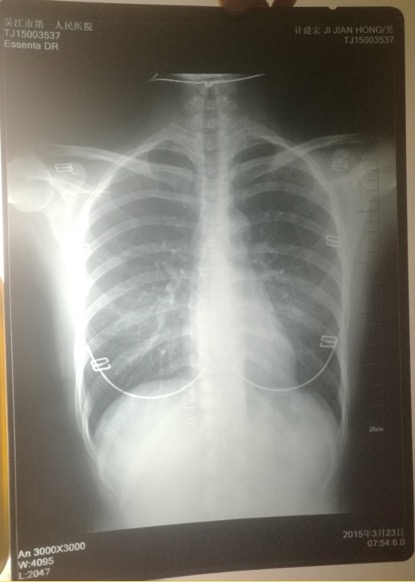

印有計建宏姓名的胸片實為一名女性的。 受訪者供圖

印著父親姓名的胸片,圖像卻顯示有明顯女性文胸搭扣和項鏈的印記。

“當時我和母親都奇怪,一年多前體檢正常,怎么這么快腫瘤長得如此大了?”更令計云強疑惑的是,該院胸外科主任在系統(tǒng)中輸入計建宏姓名后,查詢得到的胸片,可明顯看出有女性文胸的搭扣和項鏈,“后來醫(yī)生含糊地說可能是同名同姓,便不讓我看了。”

“7月初,我們回到吳江,帶著滿心悲傷和疑慮去了體檢科,想搞清楚父親的胸片究竟是怎么回事。”計云強稱,此后幾經周折,在找了吳江區(qū)第一人民醫(yī)院體檢科、投訴科等多個部門后,耗時多月,才被體檢科通知去拿父親的胸片,“一張是我父親的名字,但有文胸印記;另一張是醫(yī)院所謂的我父親的胸片,顯示的是其他人的姓名。”